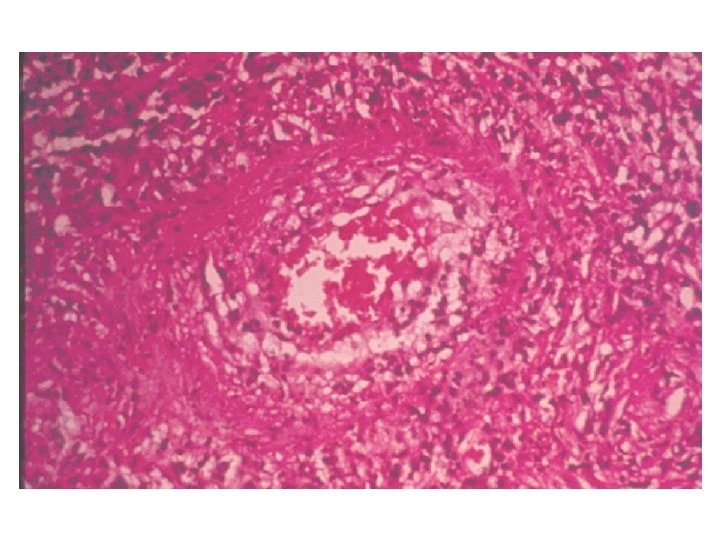

IMUNIDADE A BACTÉRIAS INTRACELULARES Imunidade resultando em cura Mycobacterium tuberculosis Rx de tórax mostrando calcificação no hilo pulmonar esquerdo após cura da tuberculose primária Alteração da resposta imune resultando em lesão Mycobacterium leprae pólo tuberculóide pólo lepromatoso M. tuberculosis Granuloma pulmonar